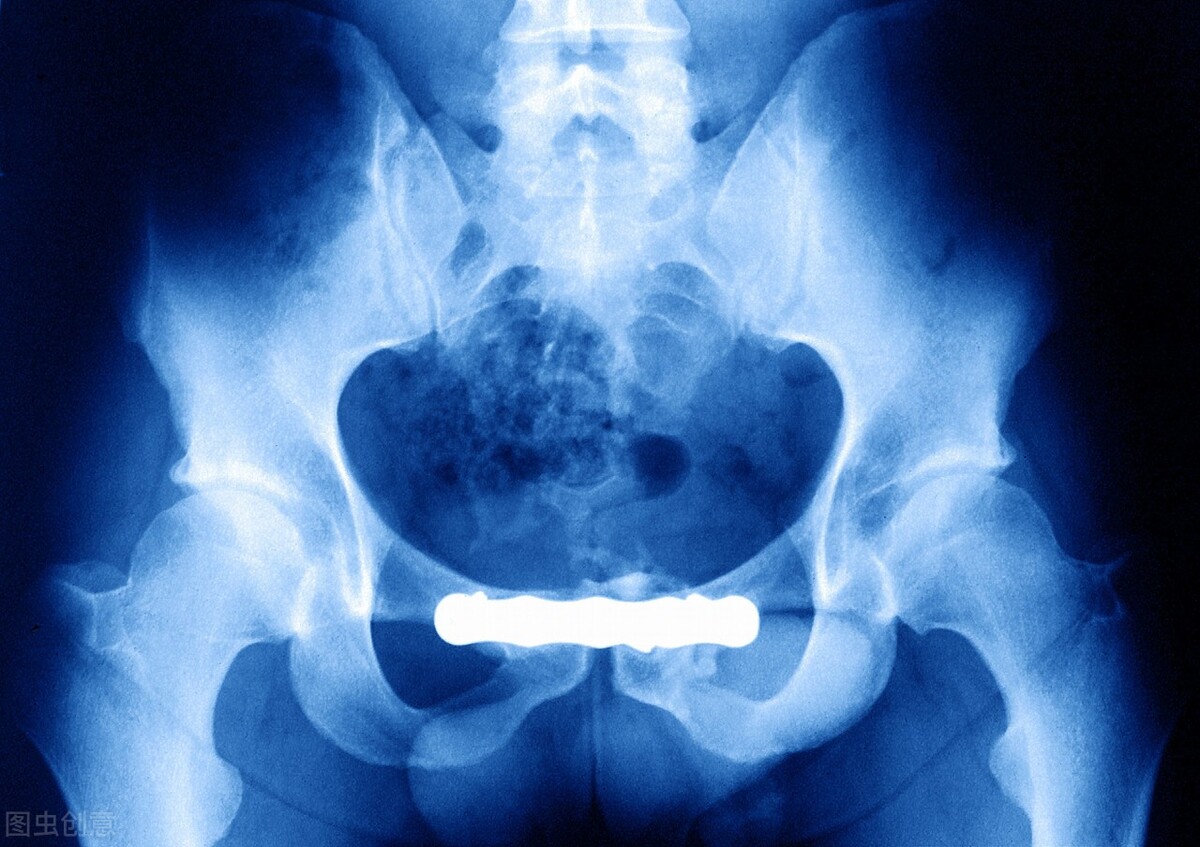

前段时间,陈先生的髋关节越来越疼,有时候睡到半夜都会被疼醒,后来连蹲下都很困难。这天,他趁着公司放假,一个人前往医院就诊。经过一番仔细的检查,医生诊断陈先生患有股骨头缺血性坏死,并伴有髋关节关节炎。

股骨头是左右髋关节的重要组成部位,它在盆骨下方、大腿根部,具有承上启下的功能。一旦于股骨头的血液供应受到干扰或破坏,可能会引起骨组织损坏,如果这时候出现结构改变、股骨头塌陷变形、关节炎症、功能障碍等情况,可能会造成股骨头坏死。

上述症状都是股骨头坏死的表现,但这种表现其实并不具有很强的特异性,要想确认是否患有股骨头坏死,还需要做进一步的镜像学检查,比如做磁共振检查来进行确诊。